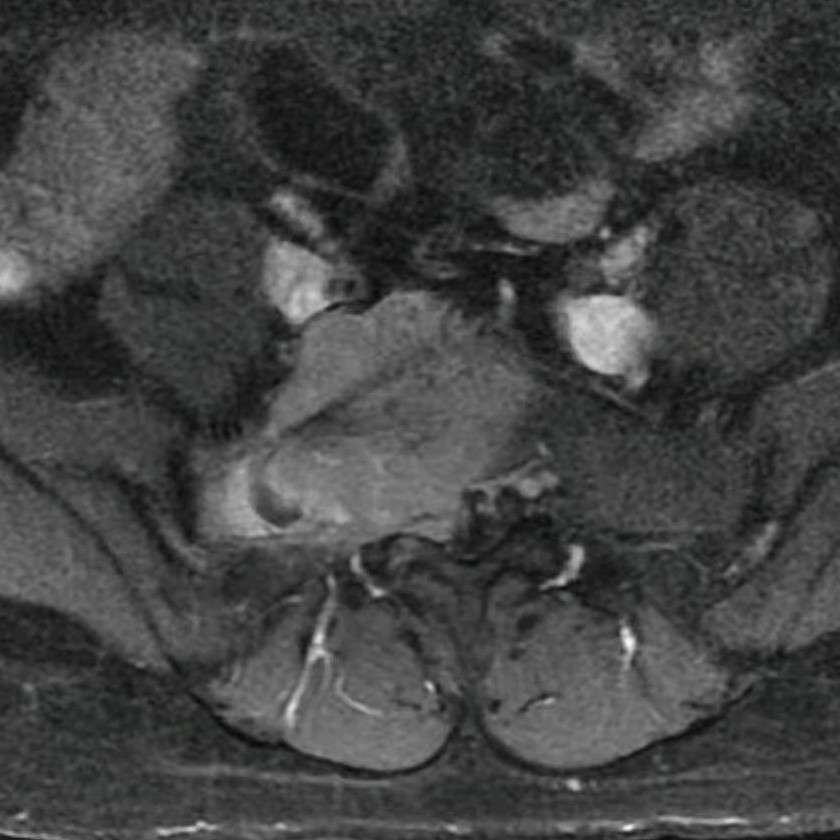

患者是一名39岁女性,1月前因右下肢疼痛麻木无力在当地医院就诊,行核磁共振检查显示骶1椎体肿瘤向椎管内及骶前膨胀性生长,压迫神经。患者辗转多家医院,均未得到可行的手术方案。经过多方打听、反复咨询并结合自身曾在交大一附院做过腹膜后肌肉瘤手术的就医体验,患者最终慕名来到我院骨科,求助于骨与软组织肿瘤韩学哲、边卫国教授团队。